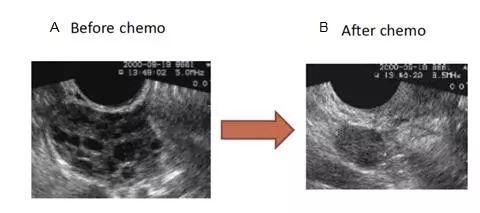

图4.化疗前后卵巢的超声对比图(图片来源:Claus Yding Andersen, Laboratory of reproductive biology,University of Copenhagen, Copenhagen, Denmark)。图4A是化疗前正常的卵巢超声图,卵巢大小正常,可见多个卵泡;图4B是化疗后的卵巢超声图,卵巢萎缩,未见卵泡。